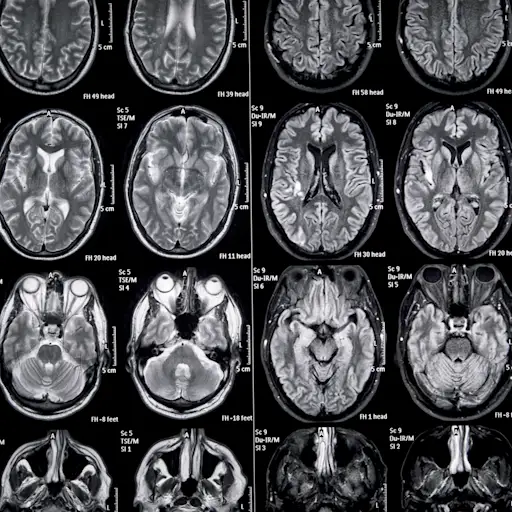

病变或斑块

Giesser博士说,多发性硬化症中最常用的术语之一是病变。例如,你可能会在核磁共振检查后听到你的大脑有损伤,这听起来很可怕。她补充说:“我告诉人们,病变只是意味着那里有一些不该有的东西,但它通常像雀斑,而不是肿瘤。”无论是病变还是斑块,这些病变通常发生在大脑和脊髓的部分区域,在这些区域,被称为髓鞘的神经保护鞘被剥离,导致神经损伤。